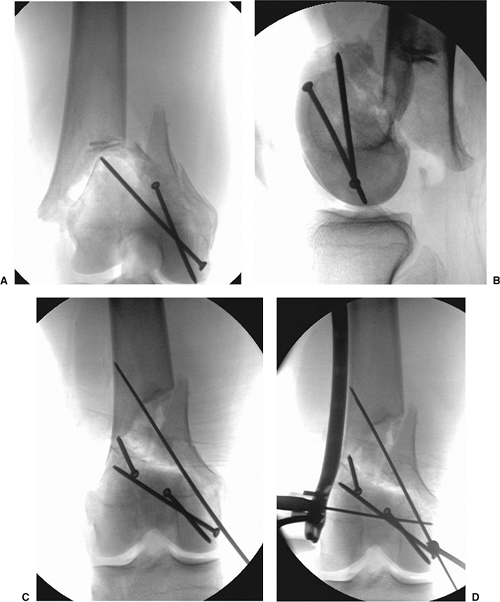

stabilized prior to reduction of the intercondylar component. For

coronal plane fractures of the lateral femoral condyle, the articular

surface can be reduced and compressed with a pointed clamp, followed by

placement of lag screws (Fig. 23.9). The

location and angulation of the fracture plane determine the direction

and location of the screws. Usually, 3.5-mm lag screws can be placed

from anterior to posterior, perpendicular to the fracture, and

angulated approximately 10 degrees from medial to lateral. The screw

heads should be countersunk beneath the patellofemoral articular

surface when necessary.

angulation of up to 25 degrees from lateral to medial may be required.

Two screws are usually adequate for simple coronal plane fractures. The

Figure 23.9.

Associated comminution in the coronal plane occurs more commonly at the lateral femoral condylar and can be stabilized with lag screws placed perpendicular to the fracture line. A. The anterior to posterior direction is usually preferred. In this example, (B) the lateral coronal fracture is first reduced and held with a clamp. C. Lag screws are then placed perpendicular to the fracture. D. The intercondylar component of the fracture can then be reduced, clamped, and temporarily stabilized with K wires. E. Lag screws can then be placed from lateral to medial to allow removal of the clamp and K wires and to ease with the plate application. The lateral locked plate can then be secured to the (F) distal and (G) proximal segments. |